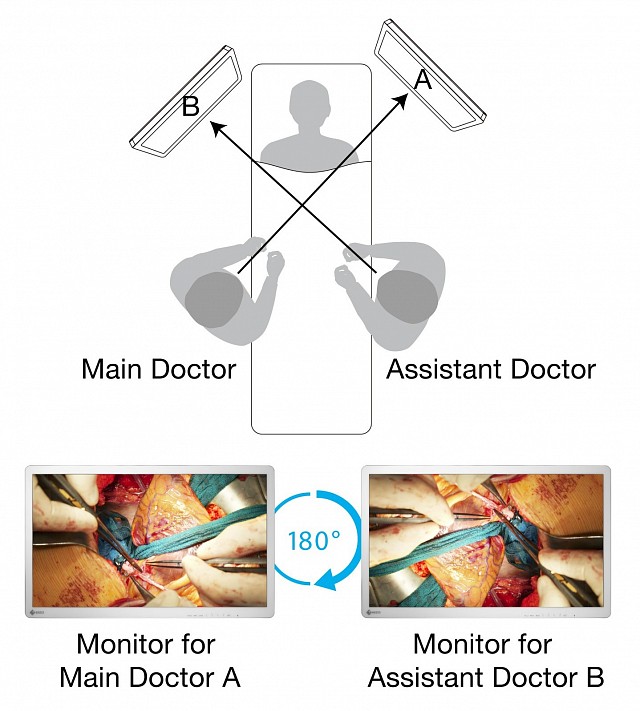

具有4K UHD(3840 x 2160像素)分辨率和高亮度的32英寸宽屏手术监视器。

EX3241具有4K UHD(3840 x 2160像素)分辨率和高亮度的32英寸宽屏手术监视器。